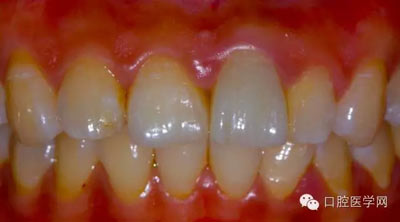

4、復(fù)診時戴臨時冠的牙齦恢復(fù)情況,恢復(fù)良好

5、3MU200樹脂粘接劑粘固全瓷冠術(shù)后照

6、術(shù)后一周照,牙齦恢復(fù)良好